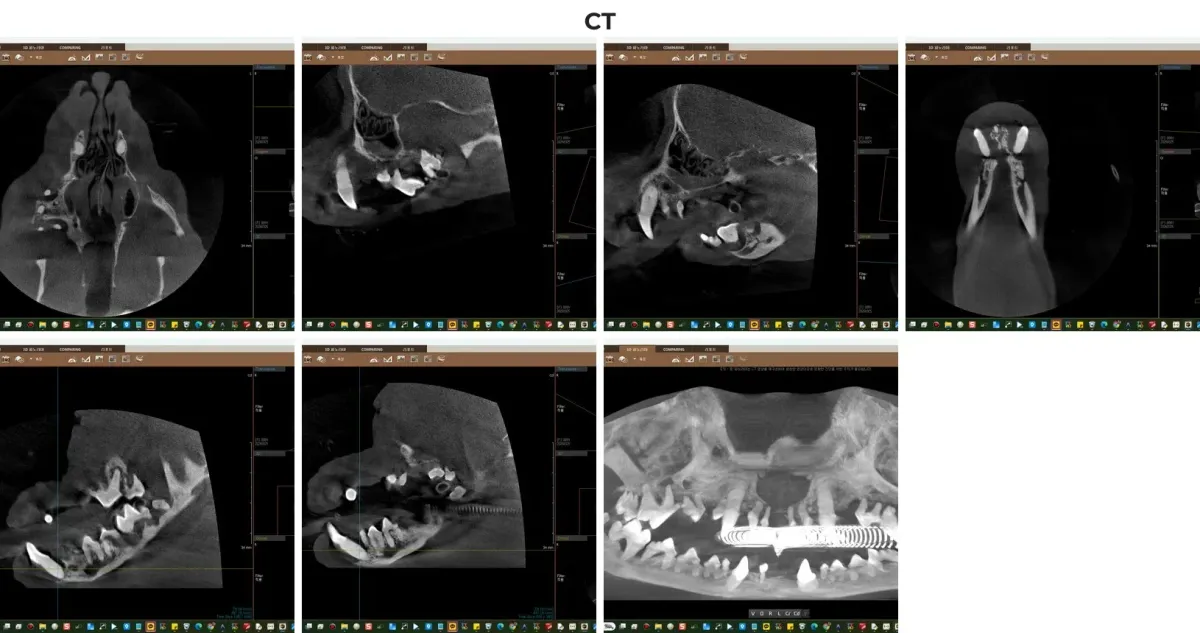

정확한 치조골(잇몸뼈) 상태와 뿌리 염증을 평가하기 위해 디지털 구강 방사선(X-ray) 촬영과 더불어 광주 전남 유일 동물전용 치과 CT 촬영을 진행했습니다.

치주염이 고도로 진행된 소형견의 경우, 겉으로 보이는 치아 상태보다 잇몸 아래의 치조골 흡수(잇몸뼈가 녹는 현상)가 훨씬 심각한 경우가 많습니다. 일반 엑스레이 평면 영상만으로는 겹쳐 보이는 해부학적 구조 때문에 진단에 한계가 있지만, 광주 전남 유일 치과 전용 CT를 활용하면 3D 입체 영상으로 뼈가 녹은 깊이와 주변 신경관과의 거리를 0.1mm 단위로 정확히 파악할 수 있어 안전한 수술 계획 수립이 가능합니다.

광주 전남 유일 치과 전용 CT를 통해 확인한 우유의 3D 잇몸뼈 흡수 소견

검사 결과는 다음과 같이 종합되었습니다.

• 치아 소실(Missing): 이미 13개의 치아(101, 106, 110 등)가 저절로 빠져 사라진 상태

• 중증 치주염(PD4 단계): 상하악 송곳니 4개(104, 204, 304, 404)를 포함한 다수의 치아에서 치아 흔들림과 극심한 치조골 흡수 확인

• 잇몸 종양 발견: 우측 상악 제1전구치(105번) 부위 잇몸에서 작은 종양성 증식(Gingival Tumor) 발견